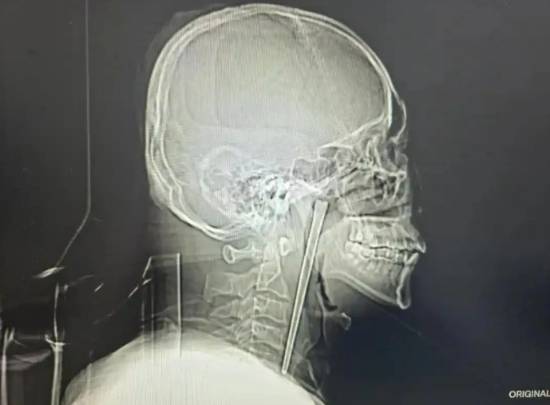

近日,大连理工大学附属中心医院耳鼻咽喉头颈外科接诊了一位特殊患者,46岁的王先生因咽部突发疼痛、异物感难忍前来就诊,一根长达12厘米的金属筷子竟在他的咽部“藏”了整整8年。

8年前,王先生意外误咽了一整根金属筷子,当即出现颈部哽咽感。医院先为其进行简单处理,暂时缓解急性不适,但后续需要切开侧颈部才能将筷子取出,因对该手术方式心存顾虑,王先生最终放弃了治疗,这根金属筷子也就此滞留在了咽部。

考虑到王先生8年前因顾虑颈部切开手术的创伤而放弃治疗的过往,在刘得龙主任指导下,黄巍鹏医生为其定制经口腔取异物的微创手术方案取出。